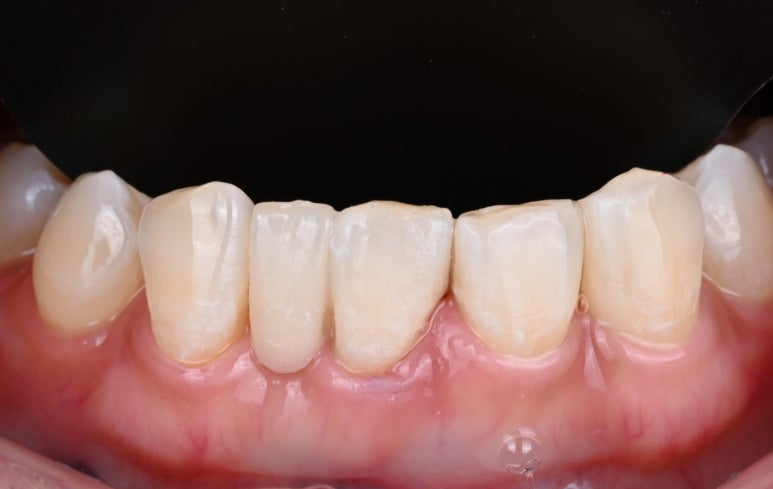

4. 치료 결과

"진작 할 걸 그랬어요!"

26.04.02 치료 후 모습

치료가 끝난 후,

환자분께서는 거울을 보며

한참 동안 미소를 지으셨습니다.

평생을 따라다니던 콤플렉스가

며칠 만에 해결되었기 때문입니다.